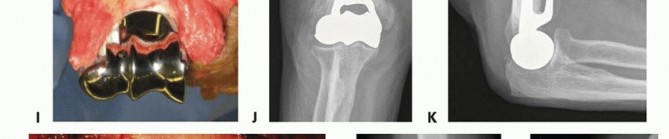

TECH FIG 4 •(continued)I-K. Latitude DHH. I. Intact medial and lateral humeral columns, with a red vessel loop loosely around the ulna nerve. J. AP radiograph demonstrating the trochlea and capitellum correctly sized for the host, greater sigmoid notch of the ulna, and the radial head. K. Lateral radiograph demonstrating a well-aligned radio capitellar joint and osseous integration of the anterior flange. L-N. Sorbie DHH. L. Fractured medial and lateral columns were reconstructed with K-wires, prior to implant insertion. M. AP radiograph demonstrating a well-seated Sorbie implant with healed medial and lateral columns. N. Lateral radiograph demonstrating a well-aligned radiocapitellar joint with posterior heterotopic ossification in the traumatically injured triceps muscle.